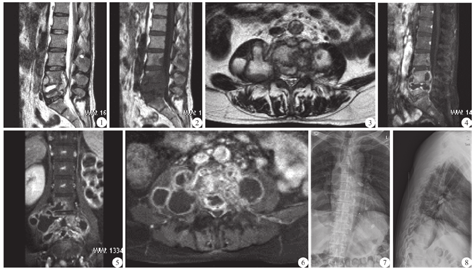

120例中,发生于颈椎例15例(12.5%),胸椎20例(16.7%),腰椎57例(47.5%),胸腰段26例(21.7%),骶椎2例(1.7%),大部分是椎体结核(105/120,87.5%),少部分累及附件(15/120,12.5%),单纯附件结核很少见(6/120,5%)。单个椎体受累6例,2个椎体受累20例,94例显示3个及以上椎体受累。最多受累8个椎体(图1,图2,图3,图4,图5,图6,图7,图8)。

120例脊柱结核,MRI诊断准确112例,准确率为93.3%。其MRI表现如下:(1)椎体及附件表现:椎体骨质破坏120例,共累计椎体368个,椎体及附件骨质破坏表现为T1WI大部分为低信号,少数是以低信号为主的混杂信号,T2WI上92%为高信号,骨髓水肿表现为T1WI稍低信号,T2WI为高信号或者混杂信号;骨质破坏区内常见斑点状或斑片状死骨,表现为T1等信号,T2低信号,T2压脂像为低信号。24.2%病例椎体骨质破坏呈楔形或变扁,椎体终板破坏表现为低信号带中断,部分椎体(35.0%)内小脓肿形成,表现为类圆形稍长T1、长T2信号,增强扫描呈小环形厚壁强化,壁可厚薄不均,也可较均匀。(2)椎间盘表现:103例椎间盘受累,表现为椎间隙狭窄或消失,椎间盘变扁,边缘模糊,表现为长T1、长T2信号。完全破坏的椎间盘往往与破坏椎体分界不清,受累椎间盘内常有小脓肿形成。(3)椎旁软组织肿胀、冷脓肿形成表现:椎旁软组织肿胀或冷脓肿MRI表现为T1WI呈低信号,T2WI呈高信号,病变范围较广,多跨越多个椎体,增强扫描呈明显环形或多房样厚壁强化;本组病例中,25例椎旁软组织均肿胀;87例冷脓肿形成,其中脓肿位于胸椎及胸腰段椎旁者30例,腰骶椎冷脓肿位于椎周8例,其中49例位于椎旁腰大肌内,16例位于椎旁椎管内形成多发囊性长T1、长T2信号,脓肿边界一般较清楚;椎前和后纵韧带下脓肿矢状面呈"哑铃状"。(4)硬膜囊及脊髓受累表现:92例出现硬膜和脊髓侵犯,大部分是由于椎体骨质破坏、椎体塌陷后移及后纵韧带下脓肿形成,导致椎管狭窄以及脊髓受压、移位。73例出现病灶向韧带下播散,表现为结节状长T1、长T2异常信号灶(图1,图2,图3,图4,图5,图6)。